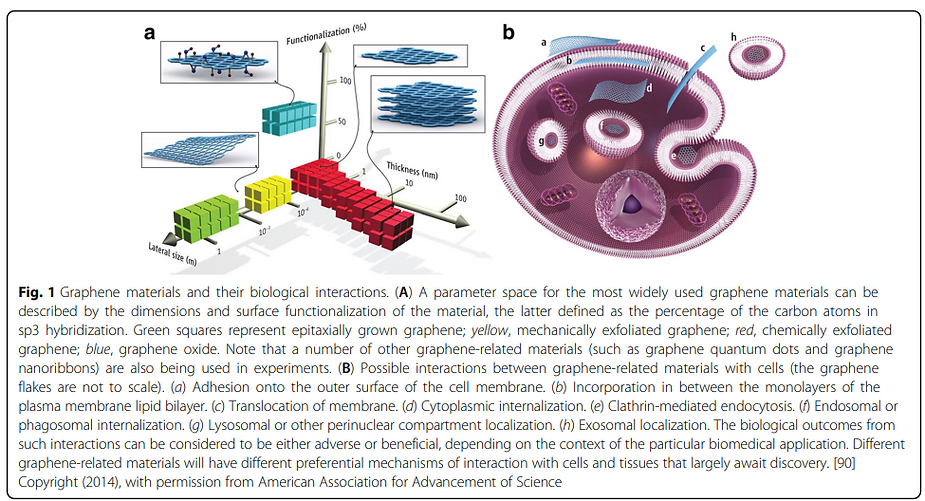

Toxicity of Graphene Family Nanomaterials

Toxicity of Graphene Family of Nanomaterials

Toxicity of Graphene Family of Nanomaterials in Cell Models

Toxicity of Graphene of Family of Nanomaterials in Cell Models

Graphene Family Nano-materials trigger local and systemic toxic effects, induce genotoxicity in vitro and in vivo, alter the gut microbiome, cause genetic mutations, and are inedible. Further toxicological and risk assessment studies are needed especially when used in food or injections of any type.

Graphene, Graphene Oxide (GO), carbon nano-tubes, and the entire graphene-family nano-materials (GFN) are toxic in almost all their forms, causing mutagenesis (cancer, chromosomal alteration), cell death, apoptosis, necrosis, and the release of free radicals.

It creates immunosuppression, damage to the central nervous system, circulatory, endocrine, reproductive, and urinary systems, which can cause anaphylactic death, and multi-organ dysfunction. It increases toxicity rapidly in the lungs, creating cytokine storms leading to bilateral pneumonia, genotoxicity, and DNA damage.

Several typical mechanisms underlying Graphene Oxide nano-material’s toxicity have been revealed in numerous studies including my own, for instance, physical destruction, oxidative stress, DNA damage, inflammatory response, apoptosis, autophagy, and necrosis. In these mechanisms, toll-like receptors, transforming growth factor-beta (TGF-β) and tumor necrosis factor-alpha (TNF-α) dependent-pathways are involved in the signaling pathway network, and oxidative stress plays a crucial role in these pathways.

Several typical mechanisms underlying graphene oxide nanomaterial’s toxicity have been revealed, for instance, physical destruction, oxidative stress, DNA damage, inflammatory response, apoptosis, autophagy, and necrosis. In these mechanisms, toll-like receptors (TLR), transforming growth factor-beta (TGF-β) and tumor necrosis factor-alpha (TNF-α) dependent-pathways are involved in the signaling pathway network, and oxidative stress plays a crucial role in these pathways.